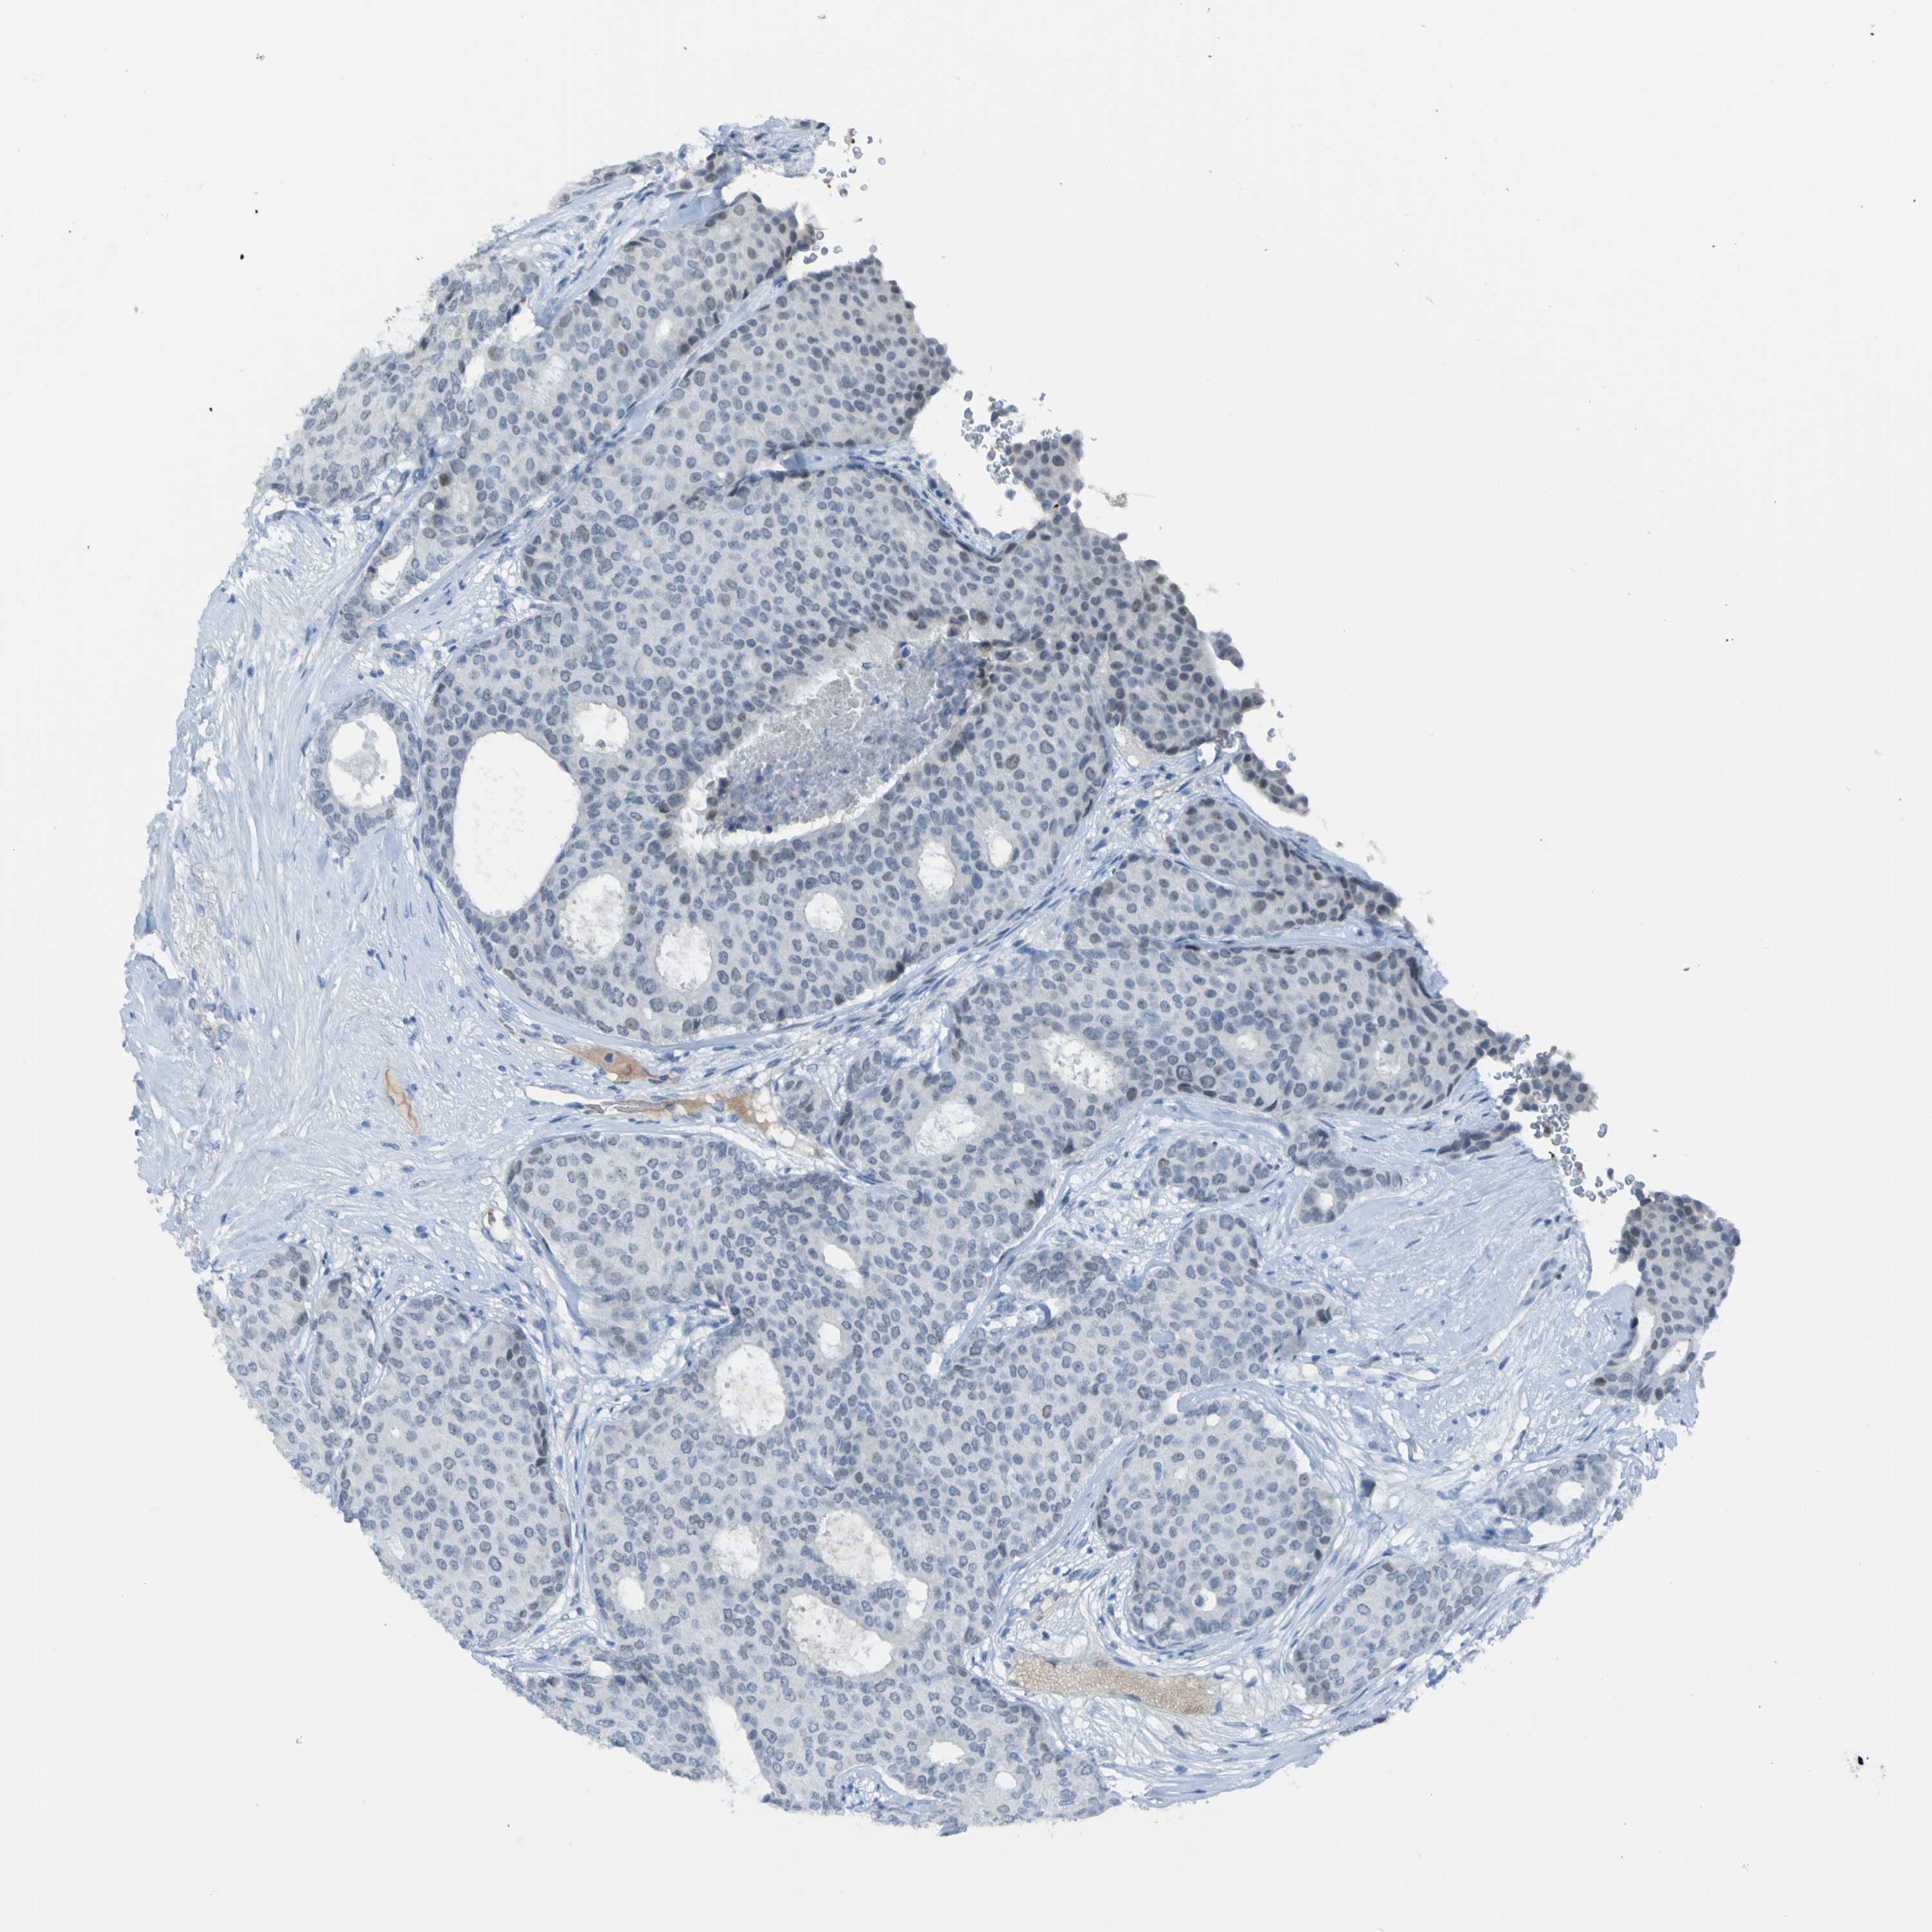

CANCER BREAST CANCER Show tissue menu

BRCA TCGA BRCA VALIDATION PROTEIN EXPRESSION

Breast cancer

Human cancer